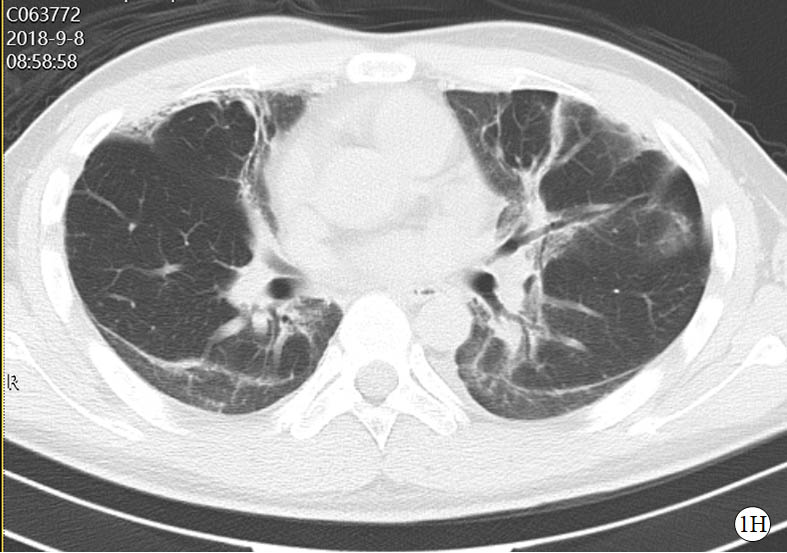

图 1 患者口服百草枯后胸部CT影像学变化

2018-09-08 CT图

2018-11-03 CT图